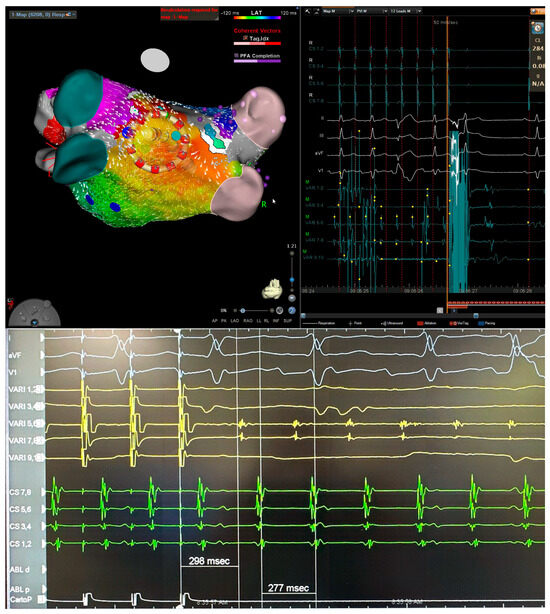

This Special Issue will provide state-of-the-art novel results of pacemaker and implantable cardioverter–defibrillator therapy, including conduction system pacing, leadless pacemakers, extravascular ICD and lead extraction. Moreover, we will provide a comprehensive state of the art of the invasive treatment of supraventricular and ventricular tachycardia, including new diagnostic tools and treatment modalities, as well as clinical results. This will also include cardio-neuro ablation for the treatment of non-cardiac syncope.